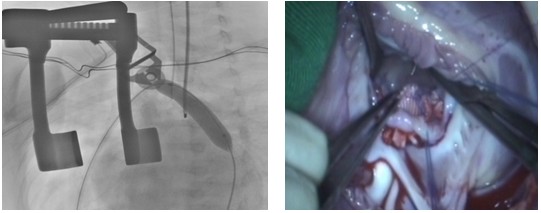

紫绀型心脏病(包括法洛四联症,肺动脉闭锁,合并肺动脉瓣狭窄的右室双出口、单心室等)通常因为肺血流量少,代偿性形成体肺侧枝,这些体肺侧枝在术前对患儿减轻缺氧症状,部分患儿甚至依靠侧支供血生存,手术前侧支循可环维持生命。但若在术中以及术后侧支依然存在,不仅增大手术操作难度,而且会对病人心肺产生巨大的伤害,所以做手术之前需要把侧支堵住。由于外科医生在手术过程中寻找体肺侧枝血管计较困难,而通过主动脉造影并封堵侧枝血管相对比较容易。两者如能协同作战,可达到简化外科手术过程 ,提高手术成功率。但传统上由于介入治疗与外科手术分家的现实,患儿需先在导管室行造影及封堵术,而后转运至外科手术行手术治疗,这不仅增加了医疗费用,而且也增加了栓塞后肺血进一步减少所潜在缺氧的风险。因此,应用兼备心血管造影及外科手术装备的“一站式”杂交手术室同期进行心血管造影及外科手术是最佳的决绝方式。最典型的例子是一位法洛四联症合并大的体肺侧支患者,其肺动脉正常血供很少,病人依靠侧支供血生存,手术前侧支循可环维持生命,但若在术中以及术后侧支依然存在,会对病人心肺产生巨大的伤害,所以做手术之前需要把侧支堵住。但当封堵侧支后,血氧饱和度从80%大幅至50%,患者出现了严重缺氧,心跳缓慢。但正是由于有了“一站式”杂交手术室,医生们立刻在5分钟内接入体外循环机,完成根治手术,病人得以救治。近年来,阜外医院法洛四联症手术成功率连续多年保持在99%以上,很大程度归功于“一站式”杂交技术的应用。此外,该技术明显缩短住院时间,并降低费用。

图注:在一站式杂交手术室内同期进行造影侧枝封堵(左)及外科手术(右)